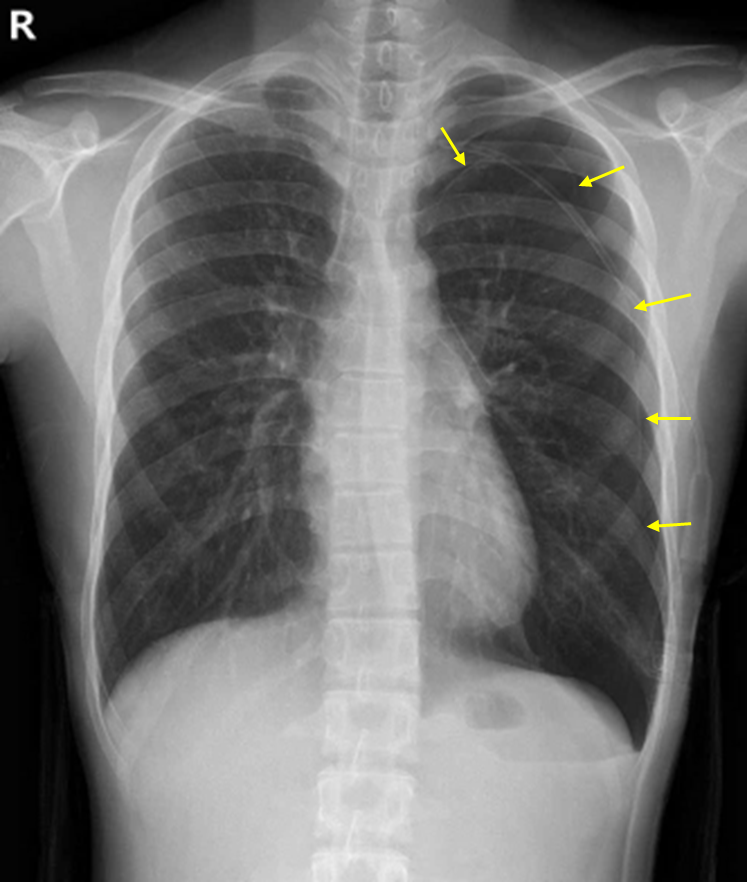

24세 남자가 5시간 전부터 갑자기 왼쪽 가슴이 아프고 숨이 찬다며 병원에 왔다. 2년 전에 같은 증상으로 가슴관 삽입을 받은 적이 있다고 한다. 4갑·년의 흡연자이다. 혈압 130/86 mmHg, 맥박 82회/분, 호흡 18회/분, 체온 36.3℃이다. 왼쪽 가슴에서 호흡음이 감소되어 들린다. 가슴관 삽입 후 가슴 X선사진과 가슴 컴퓨터단층촬영 사진이다. 치료는?

Img | CXR: Lt. pneumothorax, with chest tube inserted status CT: Lt lung apical bullae, with chest tube inserted status |

• CXR상 가슴관이 삽입되어 있는 쪽으로 visceral pleural line이 보이며, distal pulmonary vascular marking이 소실된 것이 확인된다. 이는 기흉의 전형적 소견이다.

• CT상 Lt. lung apex에 bullae가 확인된다. Spontaneous pneumothorax의 대부분의 원인은 bullae의 파열이며, 본 환자 또한 이것이 원인으로 보인다.